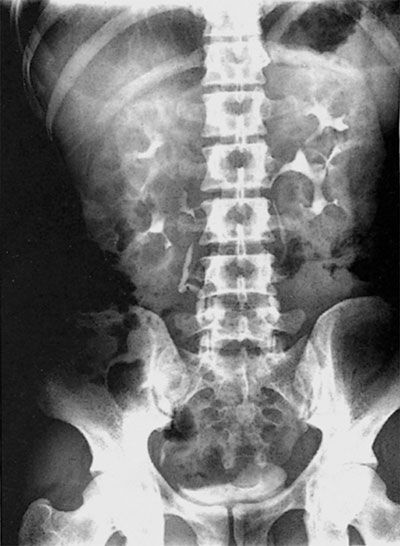

Spider leg deformity, PKD

This CECT shows the spider leg deformity in IVU. in polycystic kidney disease.... One of the major characteristics go identity PKD